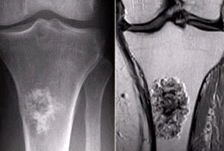

골육종(Osteosarcoma)

증상

환부 통증

,

덩어리가 만져짐

뼈의 통증

관련질환

뼈의 신생물

진료과

종양내과

방사선종양학과

소아청소년종양혈액과

정형외과